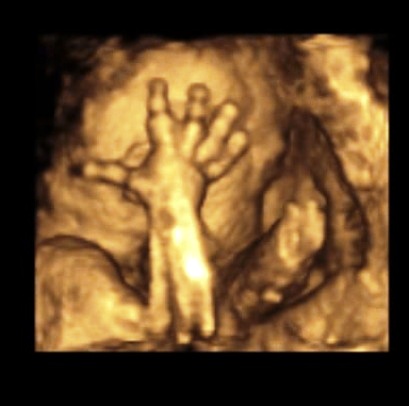

5.10.2010 - 1.UZ v poradně - 7.tt - Srdíčko krásně bije.

19.10.2010 - 2.UZ v poradně - 9.tt Fazolka má 11,1mm. Máme první foto.